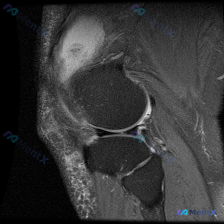

刚看到这张膝关节MRI的读片请求,主诉方向是考虑半月板异常,整理一下完整的影像观察和分析思路,和大家一起讨论。 一、影像基本信息 这是一张膝关节矢状位T2加权MRI,序列特点是:关节液、水肿、炎症呈高信号(亮白色),皮质骨和韧带肌腱呈低信号(黑色),骨髓肌肉为中等信号。 二、核心影像发现 先给大家整...